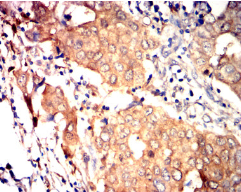

IHC    1/200 - 1/1000